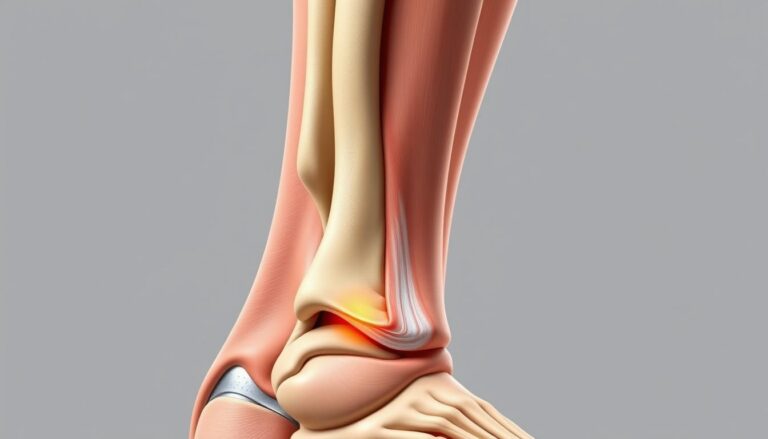

Co tak naprawdę dzieje się w naszym ciele, gdy mówimy o zroście kości po operacji haluksa? Choć proces ten może wydawać się skomplikowany, jego zrozumienie jest.

Rehabilitacja po operacji haluksa jest kluczowym aspektem, który wpływa na proces odzyskiwania pełni…